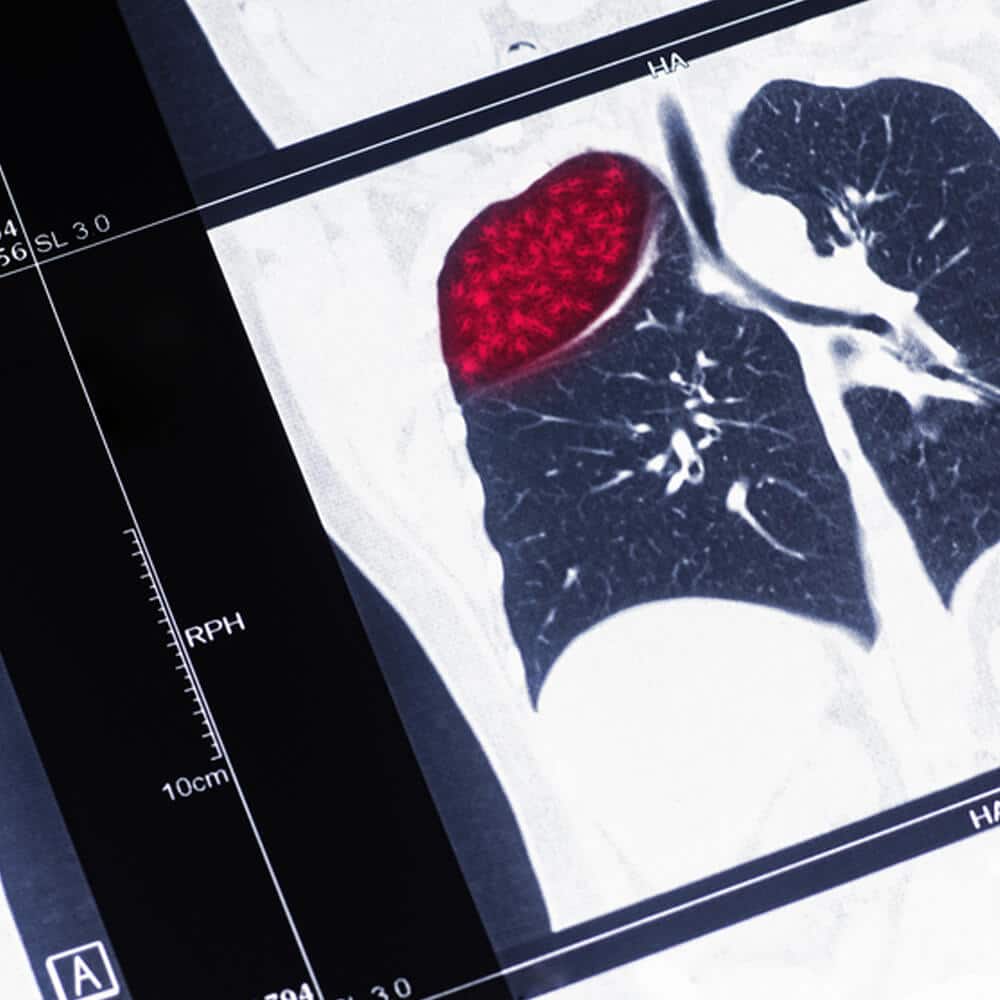

CT Lung Cancer Screening

Our CT Lung Cancer Screening uses a low radiation dose CT technique to search for lung nodules that may represent early lung cancer, especially in people who are current or former smokers. Detecting lung cancer at an earlier stage can be life-saving. This is a private, self-pay service and is not covered by OHIP. Patients aged 55–80 with a ≥20 pack-year smoking history are not eligible for private pay screening.

Low Radiation Dose Lung CT

Low-dose chest CT for lung cancer screening